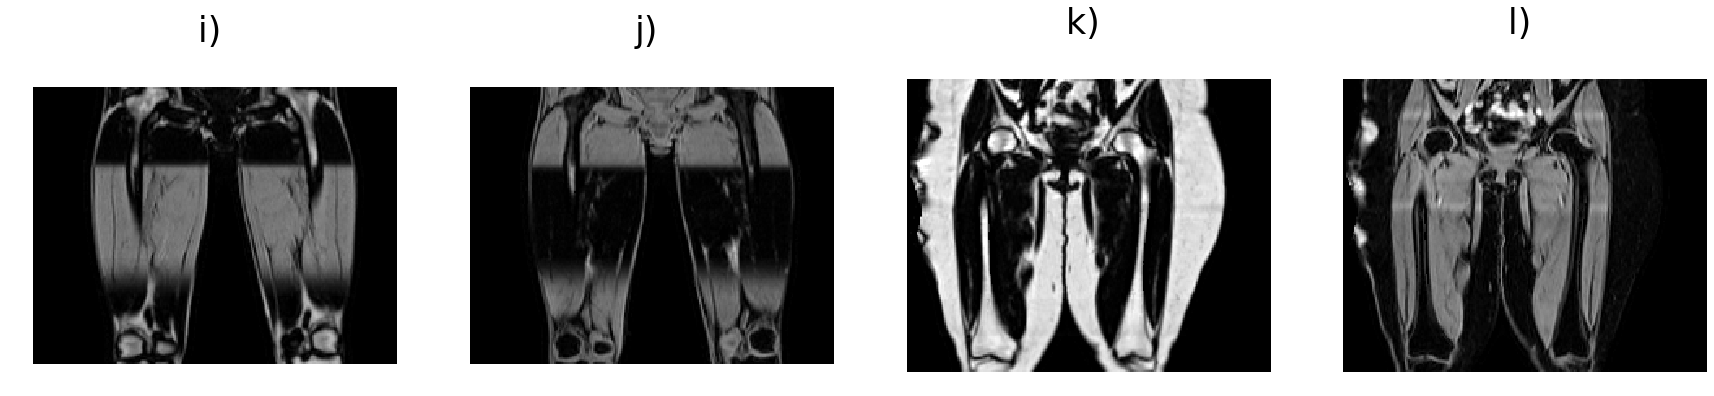

Fat and water volumes are predicted from the input volumes, illustrated in Fig. 2. The generator follows a U-Net architecture [33] with six levels consisting of 3D convolutional layers (orange) with filter size 4 and stride 2, instead of pooling layers to move to the lower resolution levels. As the full volume dimensions were simply too large to be used as is, we set the input size to in order to overcome memory limitations. The number of filters are indicated at each level in Fig. 2. Up-sampling (blue) is performed via 3D transpose convolutional layers with filter size 4 and stride 2. The number of filters are indicated at each level. The discriminator network follows a sequential architecture using 3D convolutional layers with filter size 4 and stride 2 (green) except the last two layers with stride 1 (dark green), to adjust the PatchGAN discriminator network to assess the volumes on a patch size of voxels [36].

The models for our fat-water separation experiments are based on the cGAN architecture [36], originally developed for 2D image-to-image style transfer. We define a generator such that is a direct mapping of the fat and water volumes from the in-phase (and opposed-phase) volumes, and a discriminator that jointly determines whether or not the predicted volumes are truly fat and water or not. The objective function for the cGAN is given by

| (1) |

where the loss is driven solely by the performance of the discriminator. It has been shown that additional terms in the cGAN objective function may be added to ensure the predictions are similar to the ground truth, in our case and were used as ground truth labels in the L1 loss term

| (2) |

ensuring that each individual prediction matches the ground truth data. The solution

| (3) |

is obtained by minimising the contribution of the generator to the objective function against a discriminator that tries to maximise it and the L1 term.